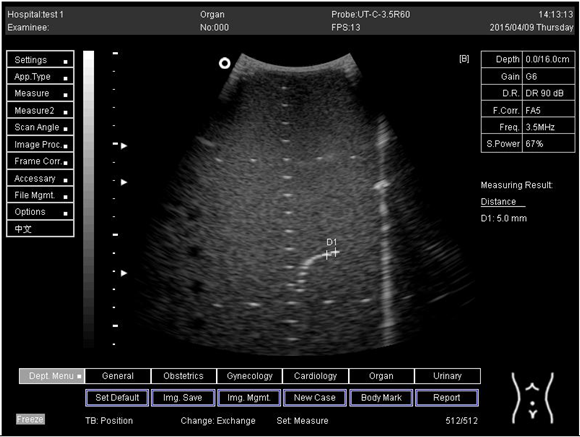

Lateral resolution

Biomimetics 07 00130 i026

D1 = 5.0